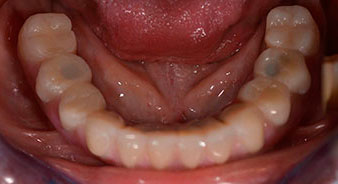

The impression and bite registration were then performed so that the dental technician could begin producing the provisional restoration immediately. This was then screwed in on the same day (Fig. 17 and 18).

Implants

Fig. 17

Fig. 18